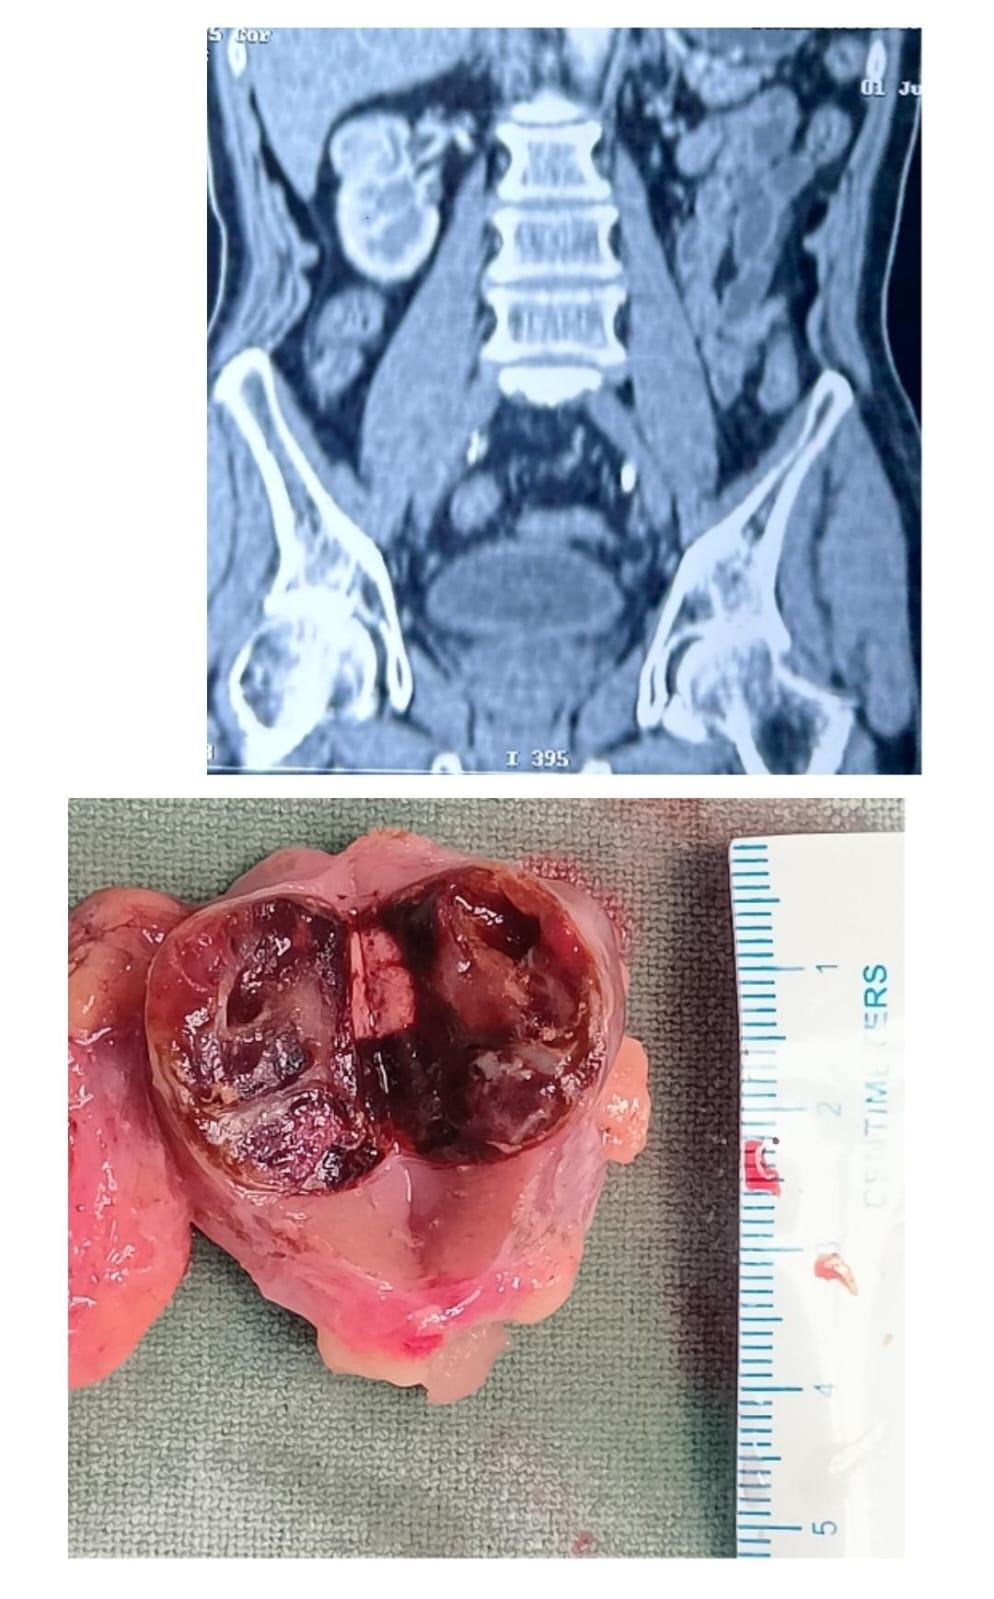

Bhubaneswar: The doctors at the Kalinga Institute of Medical Sciences (KIMS), in a complex and rare operation, saved a cancer patient by removing a portion of his kidney through advanced laparoscopic surgery. Urology Department’s Assistant Professor and HoD Sumanta Mishra, performed the surgery on a 70-year-old male patient with diabetes, high blood pressure, and chronic kidney disease. His left kidney was diagnosed with a 4 cm x 4 cm tumour. The doctors gave him the option of laparoscopic partial nephrectomy as he had multiple comorbidities. Upon his approval, Mishra and his team performed the surgery successfully. The doctors said the patient had been completely cured of cancer and the remaining kidney was working well.

KIIT and KISS founder Achyuta Samanta congratulated the doctors for the path-breaking surgery, emphasizing that providing advanced treatment with care and compassion has always been the aim of KIMS. Kidney cancer is a very common cancer today requiring early diagnosis and treatment. Radical nephrectomy or removal of the whole kidney is the treatment of choice which makes the patient live the rest of his life with only one kidney. Partial nephrectomy or removal of the cancer only part is the other option but needs specialized center for surgery, something which has now been successfully demonstrated at KIMS.